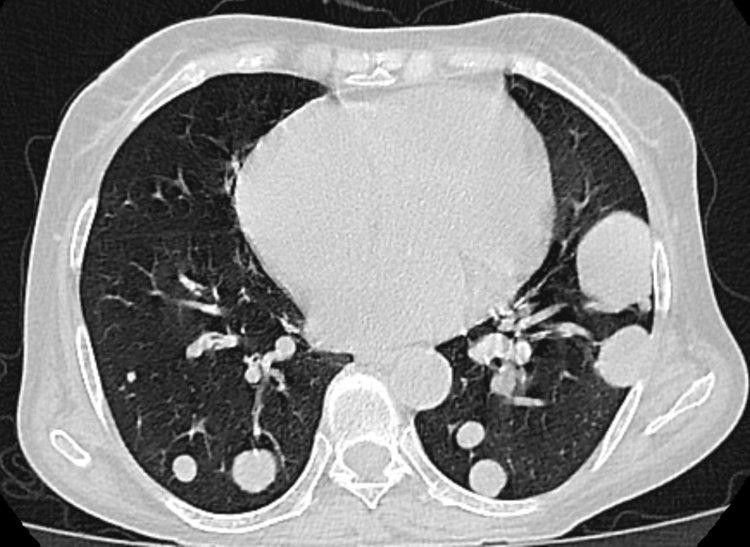

肺結節其實是指CT片上顯示的密度不同、毫米大小的陰影,它不是疾病,而是影像學上的一個詞彙。根據陰影大小可以分爲微小結節(直徑小於5毫米)、小結節(直徑5—10毫米)和結節(直徑10—30毫米)幾種分類。一般結節越大,癌變風險越高。根據陰影密度可以分爲實性結節和亞實性結節,其中部分實性結節的惡性程度最高。